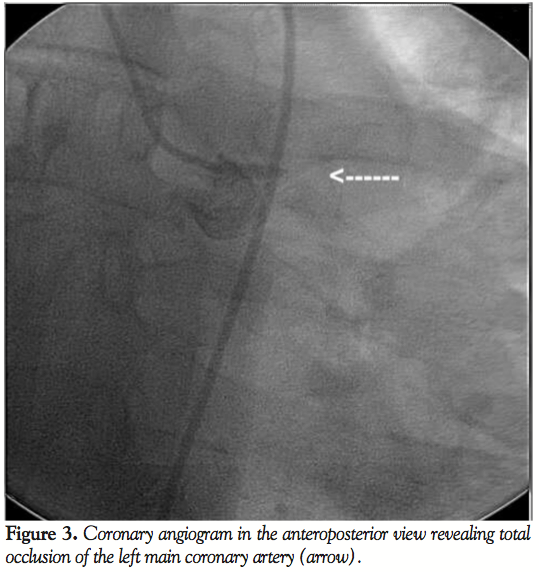

The patient’s laboratory results revealed a hemoglobin value of 13.4 gm/dL. The ECG shows normal sinus rhythm, left axis deviation, borderline left ventricular hypertrophy with nonspecific intraventricular conduction delay, and poor R progression in the precordial leads, suggestive of previous anterior wall MI (Figure 1). The echocardiogram (Figures 2A and 2B, Videos 2A-2C) demonstrated a severely depressed left ventricle ejection fraction of 25%-35% with diffuse hypokinesis of the left ventricle mild segmental wall motion abnormalities, and akinesis of the apex. There was no significant valvular pathology identified.

The cardiac catheterization revealed total occlusion of the left main coronary artery (Figure 3, Video 3A) and a dominant RCA with a 95% stenosis in the proximal segment (Figure 4, Video 4A). There were Rentrop class 2 collaterals from the right to the left coronary arteries (Figure 5, Video 5A).